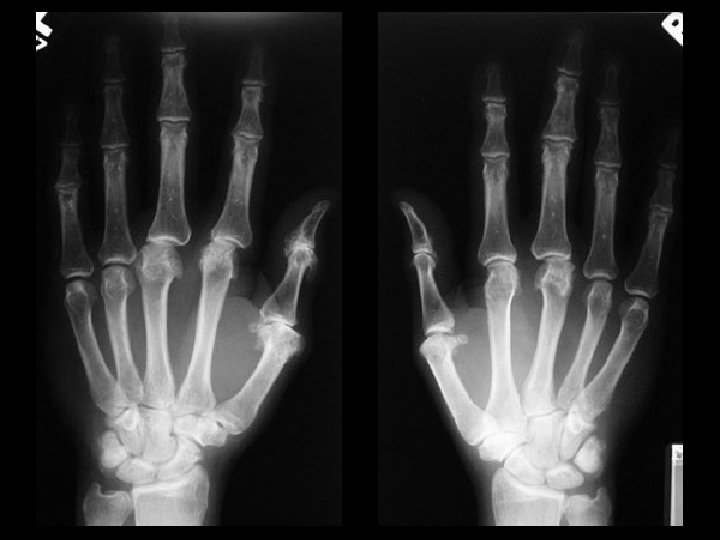

Hyperparathyroidism & Acro-osteolysis • Findings: – Erosion and resorption of digital tufts – Osteopenia with coarse trabecula – Subperiosteal bone resorption along the radial side • ddx: (acro-osteolysis) – Frostbite / Electrical burn – Polyviny chloride exposure – Pyknodysostosis – Neuropathy – Psoriatic arthritis – Hajdu-Cheney syndrome